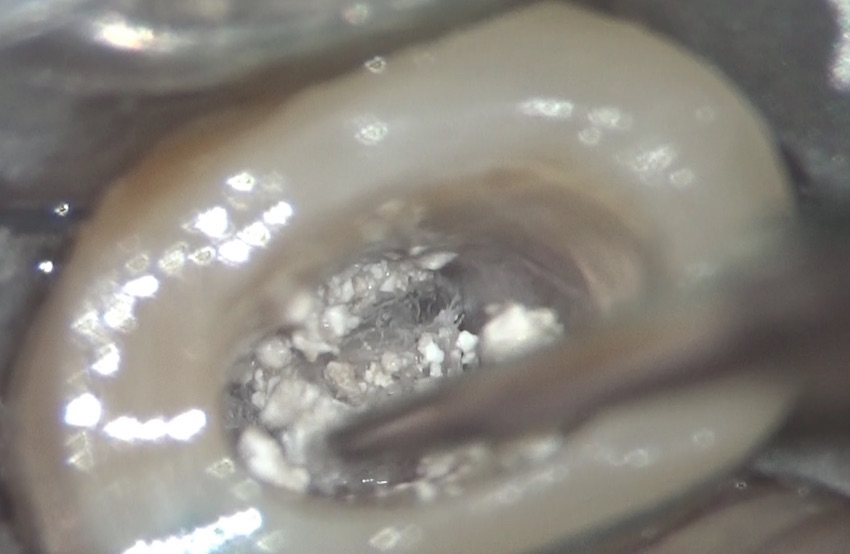

これが治療前の写真です。診査の結果、根管治療が必要と診断し、根管治療を始めました。